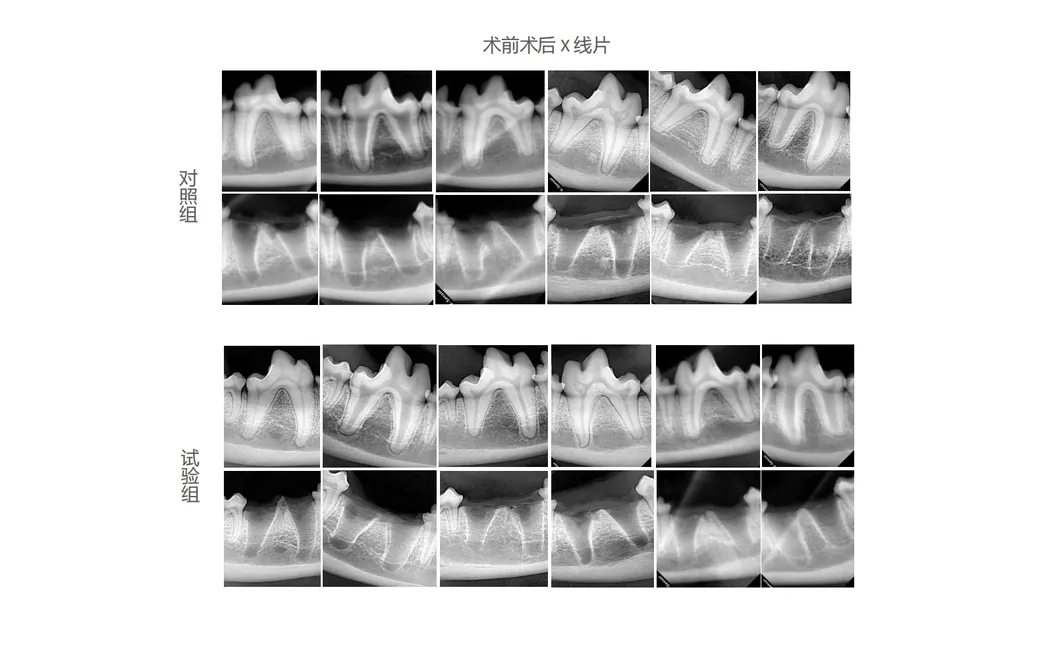

In this groundbreaking study, dogs were selected to assess the effectiveness of the Golden Cudgel-Pneumatic Dental Elevator Kit. Researchers meticulously documented physiological parameters, extraction duration, and socket damage compared to traditional manual devices. The data provides profound insights into the superior performance and efficiency of these advanced dental tools.